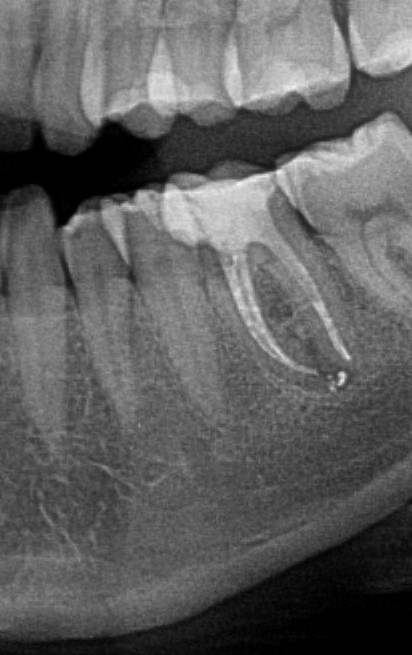

Pani Kasia z Tychów zgłosiła się z powodu resorpcji przy wcześniej leczonym kanałowo zębie. Resorpcja to nieodwracalny proces polegający na niszczeniu korzenia zęba w procesie autoimmunologicznym. Aby wyeliminowywać stan zapalny jedyną metodą jest usunięcie chorobowo zmienionego zęba. Ze względu na dolegliwości bólowe niezwłocznie przystąpiono do wykonania zabiegu usunięcia zęba, jednocześnie zabezpieczając kość pod planowany w przyszłości implant. Ubytek po usuniętych korzeniach zęba zregenerowano biomateriałem oraz odwirowanym osoczem własnym Pacjentki (PRF).

Po uformowaniu kości w miejscu usuniętych korzeni, posadowiono implant.

Pacjentka oczekuje na wykonanie korony.